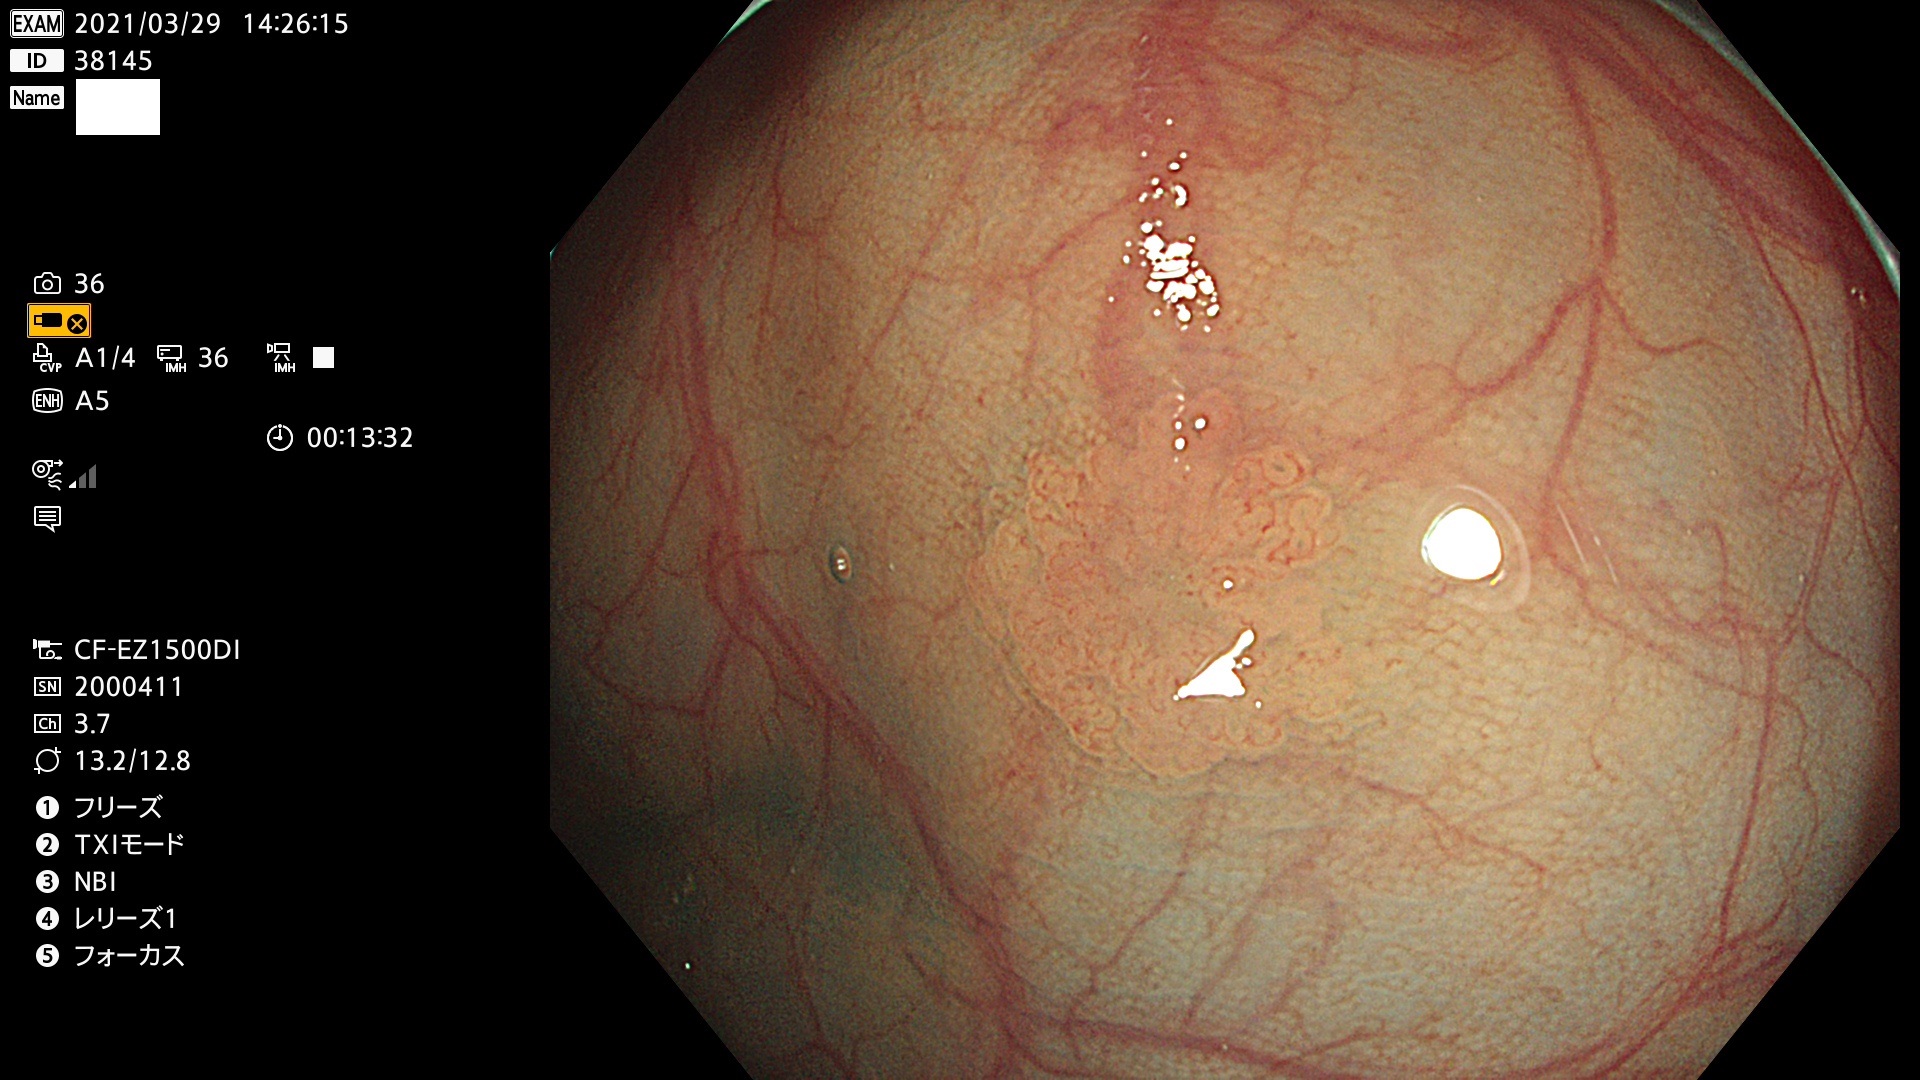

発見困難で危険性の高い平坦型病変(上記100名より抽出) ![]()